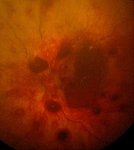

Retinal haemorrhages in abusive head trauma are usually widespread and multi-layered, as seen in this image

From the personal collection of Alice Newton, MD; used with permission